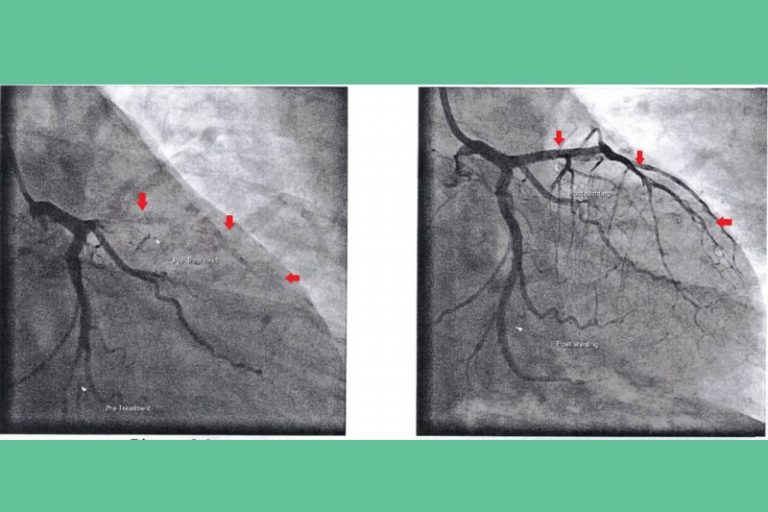

梅醫生指,病人即使完成「通波仔」手術也不是一勞永逸,研究表示有20%至50%術後病人仍有血管再次收窄的風險。因此,術後病人亦需要服用半年或以上的雙重抗血小板藥物、降膽固醇藥等,以減少冠心病再次惡化的機會。